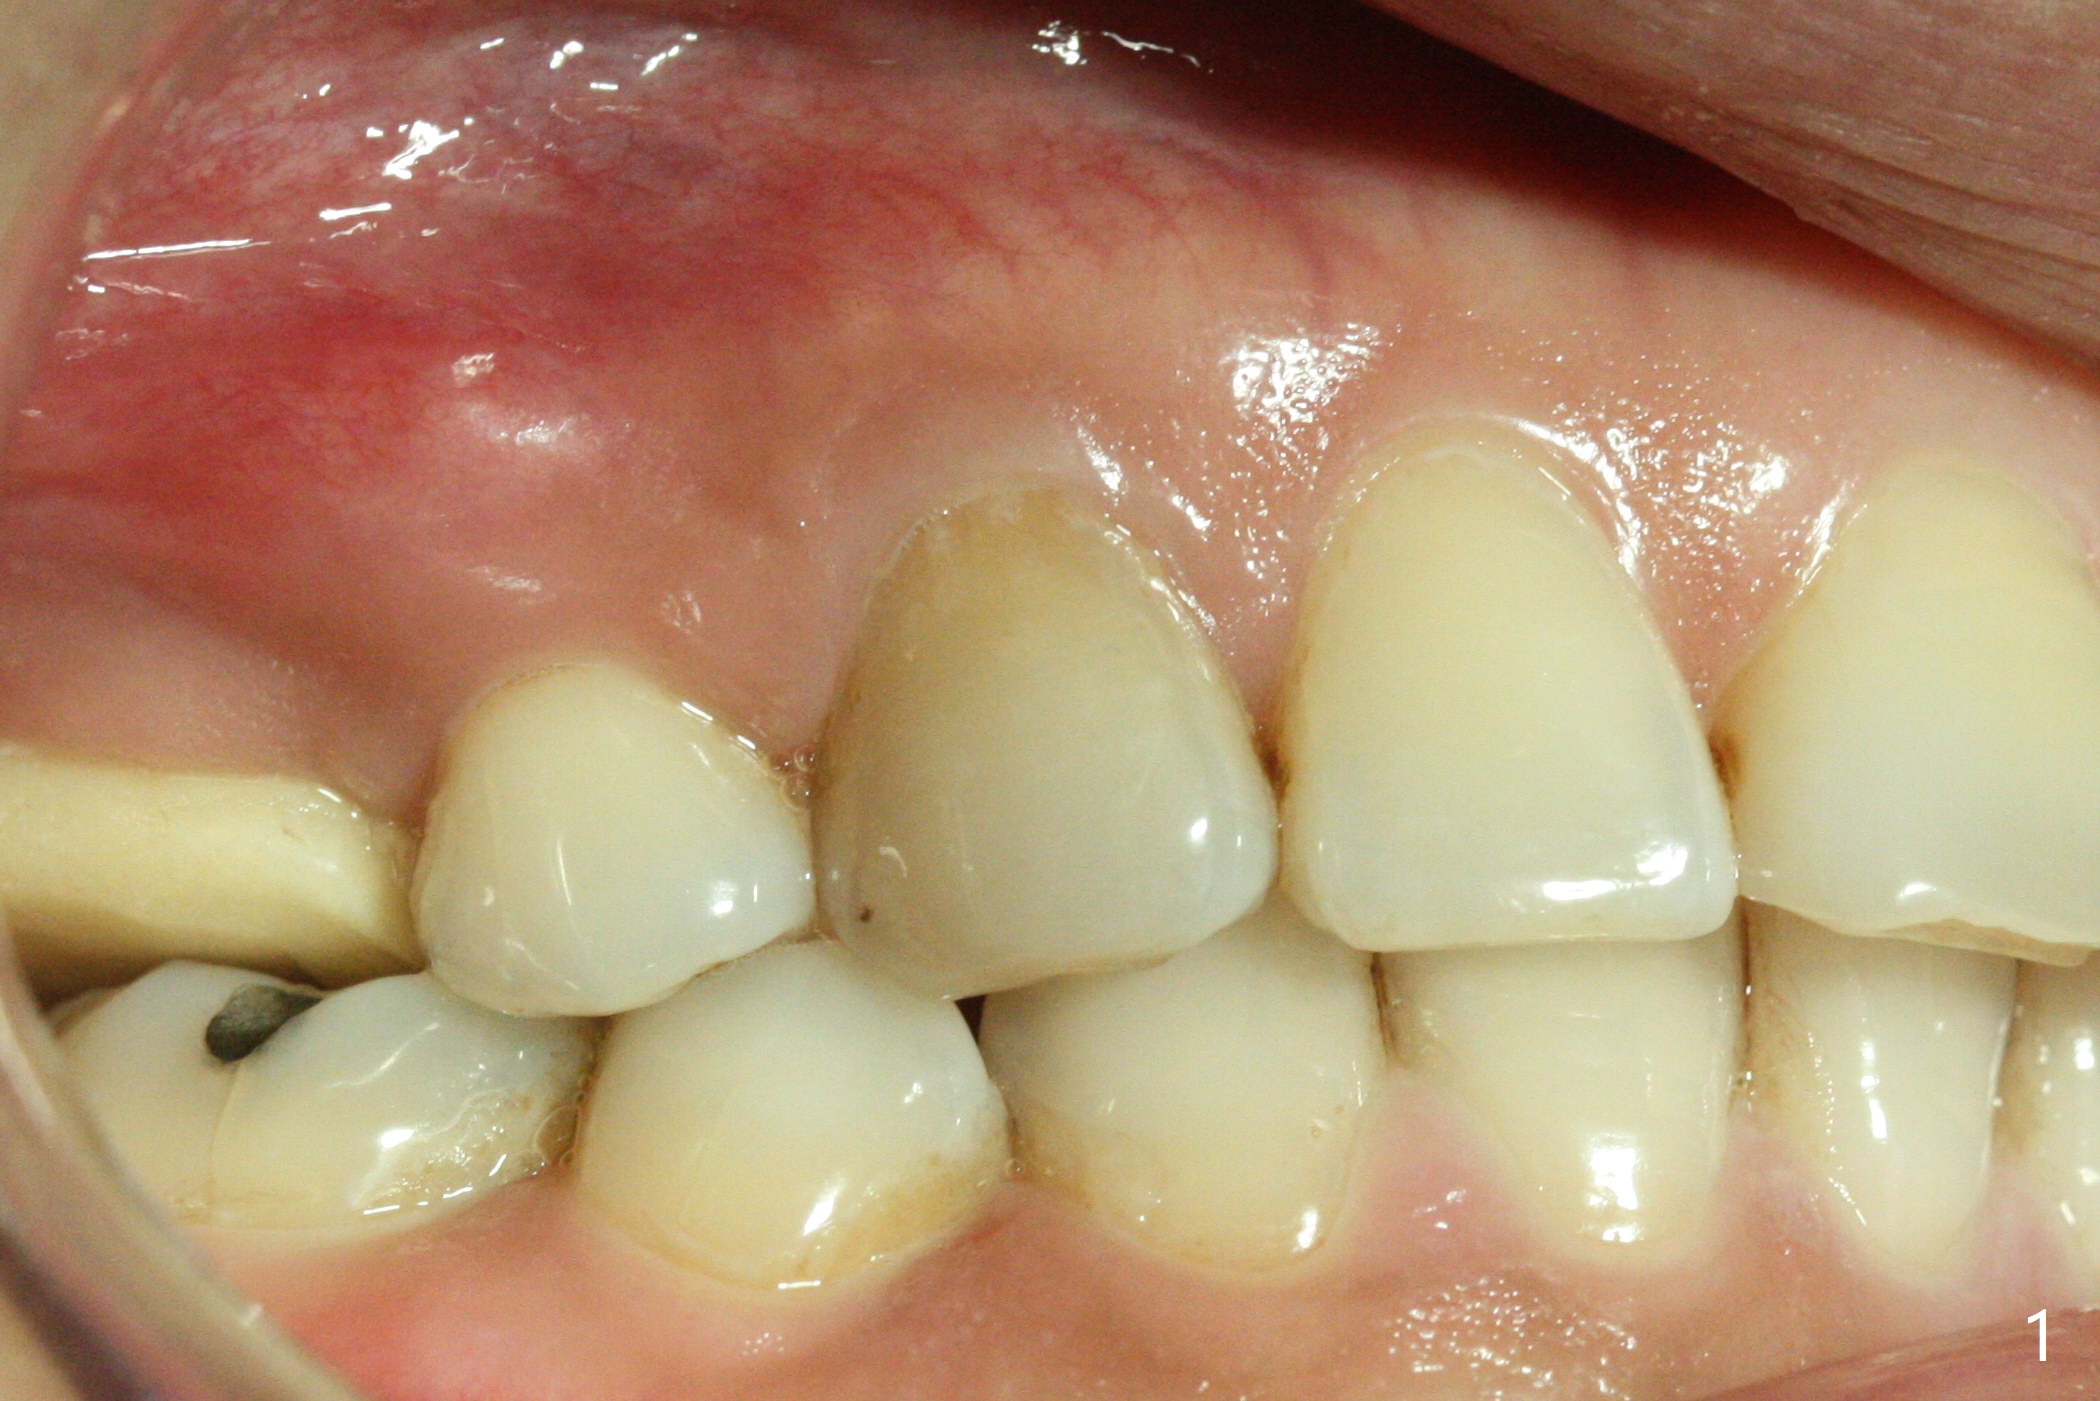

A 36-year-old woman (after #3 immediate implant and #31 socket preservation) wants to take care of the discolored canine 20 years post orthodontic treatment with extraction (Fig.1-3). RCT (Fig.4) appears to whiten the tooth (Fig.5 (A4)). The darkness appears to rebound 1 month post RCT, after removal of Gutta Percha for take home internal and external bleaching (Fig.6). The patient returns for composite after 3-week whitening (Fig.7,8). The shades of composite are bleach (flowable, C1) and B1 (packable, C2, Fig.9). The shade of the RCT tooth is compatible with that of the neighboring teeth 4 months post composite (Fig.10) when the implant at #3 has a new abutment.